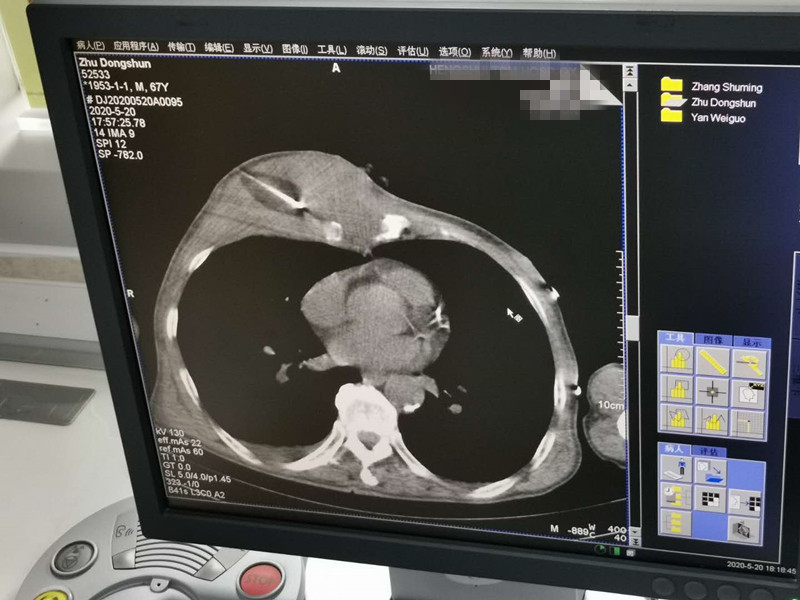

67岁胸部肉瘤氩氦刀冷冻消融

发布人:美国氩氦刀技术官方网站    发布时间:2020/5/21 14:53:37